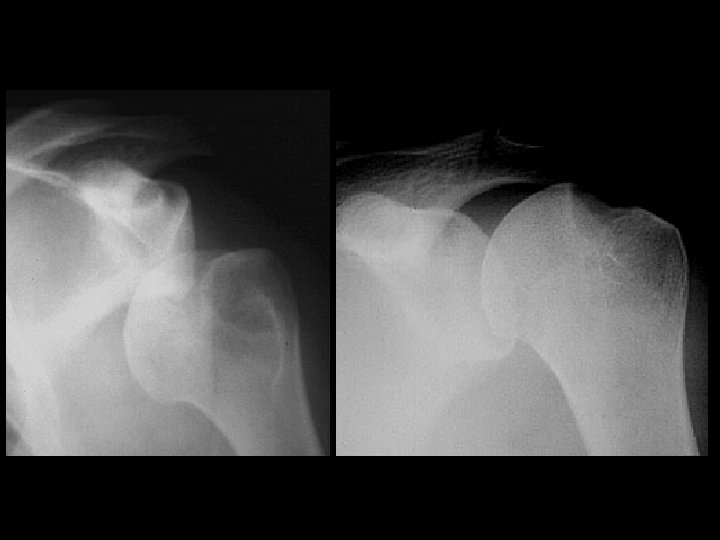

Anterior Shoulder Dislocation

Inferior shoulder dislocation • Findings: – Inferior dislocation of humeral head and a deep cleft in the superior portion • ddx: – Anterior dislocation